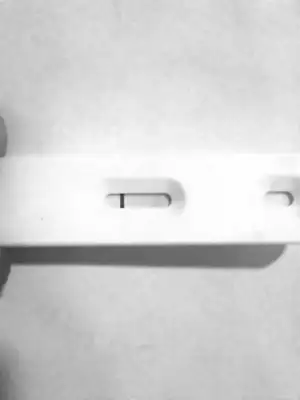

Ins cnm hayırlısı guzel haberler alırız umarım senın kacıncı gunun Pazartesi belkı dr a gıderım oda soyler olgunlasıyo dıye ıns yumurtacıklar14, 16, 19 bu günlerde pik gördüğüm olmuştu canım sabırlı ol inşAllah olacak